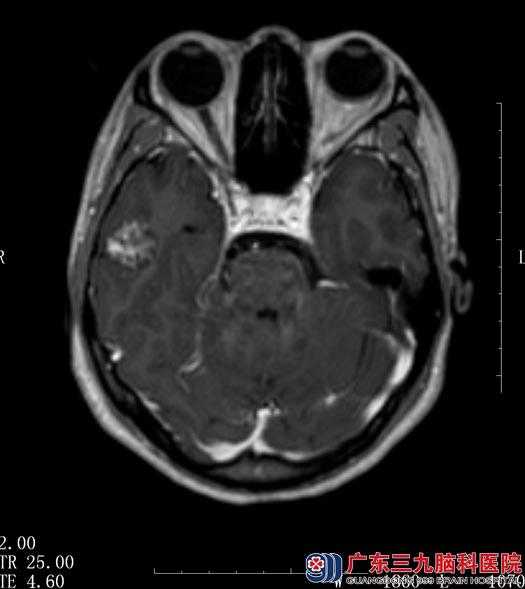

当地医院行头颅CT检查,考虑为右侧颞叶病变。入住广东三九脑科医院综合神经外科,头颅MR检查示“右颞叶占位,直径约2cm,考虑海绵状血管瘤”,动态脑电图示“右颞叶重度异常脑电反应”。

鲁明主任阅片后考虑右侧颞叶海绵状血管瘤,根据脑电图显示,陈女士的癫痫发作与海绵状血管瘤关系密切。

▲手术前